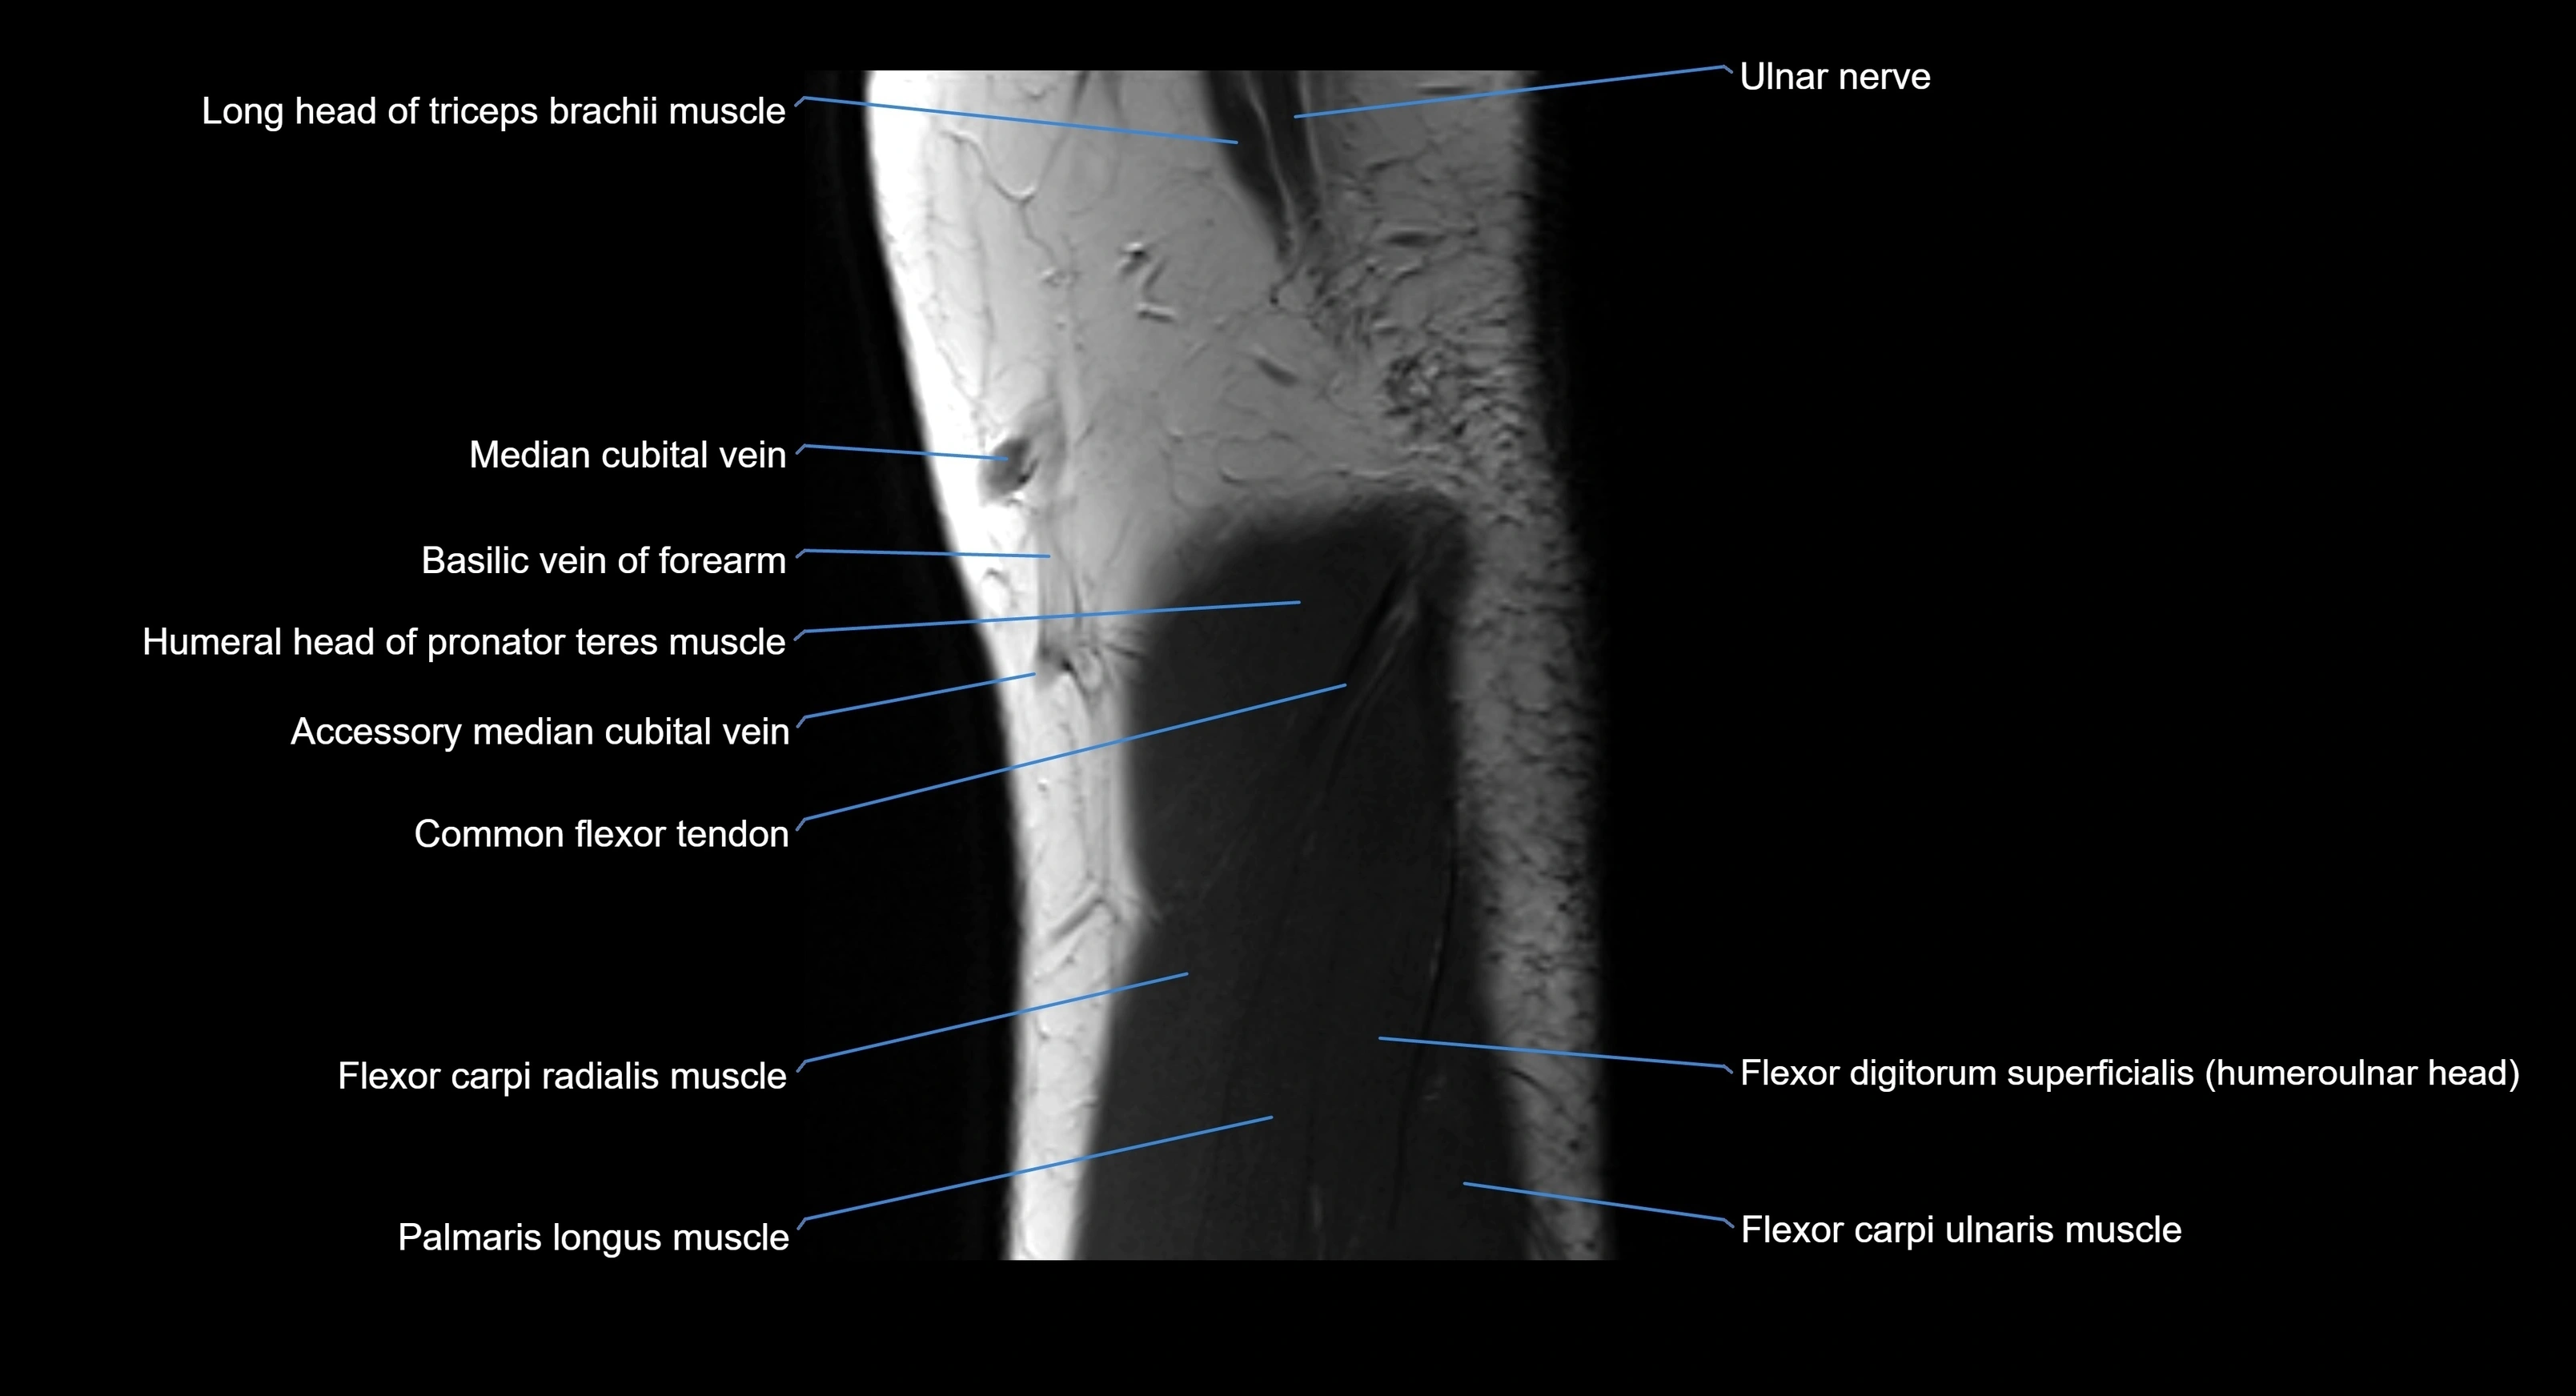

MRI image

image